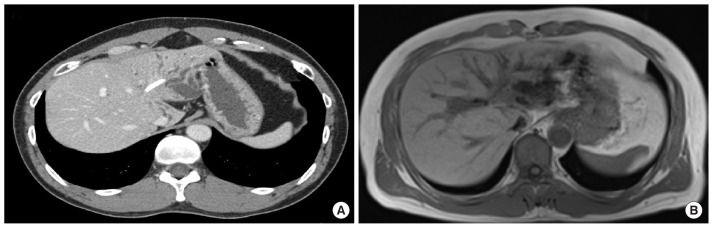

本病例研究探讨了自体细胞因子诱导杀伤(CIK)细胞免疫疗法对一名49岁男性无法手术的IIIb期胆管癌患者的有效性,该患者的特征是免疫细胞中钠依赖性维生素C转运蛋白-2 (SVCT2)水平高。尽管化疗后最初缺乏肿瘤缩小,但患者在接受放射和质子治疗后,肿瘤标志物显著减少,肿瘤稳定。随后,CIK细胞治疗联合大剂量维生素C, 6年52次。患者肿瘤缩小,诊断后7年10个月未检测到肿瘤活动,表明长期预后成功,无复发。这项研究表明,CIK细胞治疗,特别是对于SVCT2水平升高的患者,可能为胆管癌和潜在的其他癌症提供有希望的辅助治疗。需要进一步的研究来验证SVCT2作为CIK细胞治疗有效性的生物标志物。

This case study explores the effectiveness of autologous cytokine-induced killer (CIK) cell-based immunotherapy in a 49-year-old male patient with inoperable stage IIIb cholangiocarcinoma, characterized by high levels of the sodium-dependent vitamin C transporter-2 (SVCT2) in immune cells. Despite an initial lack of tumor reduction following chemotherapy, the patient showed a significant decrease in tumor markers and stabilization of the tumor after undergoing radiation and proton therapy. Subsequently, CIK cell therapy, combined with high-dose vitamin C, was administered 52 times over 6 years. The patient's tumor size reduced, and no cancer activity was detected for 7 years and 10 months post-diagnosis, indicating a successful long-term outcome without recurrence. This study suggests that CIK cell therapy, particularly in patients with elevated SVCT2 levels, may offer a promising adjuvant treatment for cholangiocarcinoma and potentially other cancers. Further research is needed to validate SVCT2 as a biomarker for the effectiveness of CIK cell therapy.